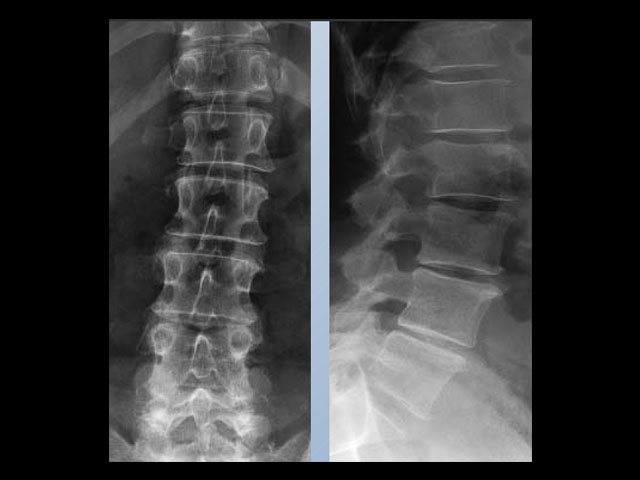

Ποτέ άλλοτε η απλή ακτινογραφία θώρακα και κοιλίας καθώς και η απεικόνιση των οστών δεν είχε την ποιότητα που επιτυγχάνεται με το σύστημα ICONOS.

Απεικόνιση 2